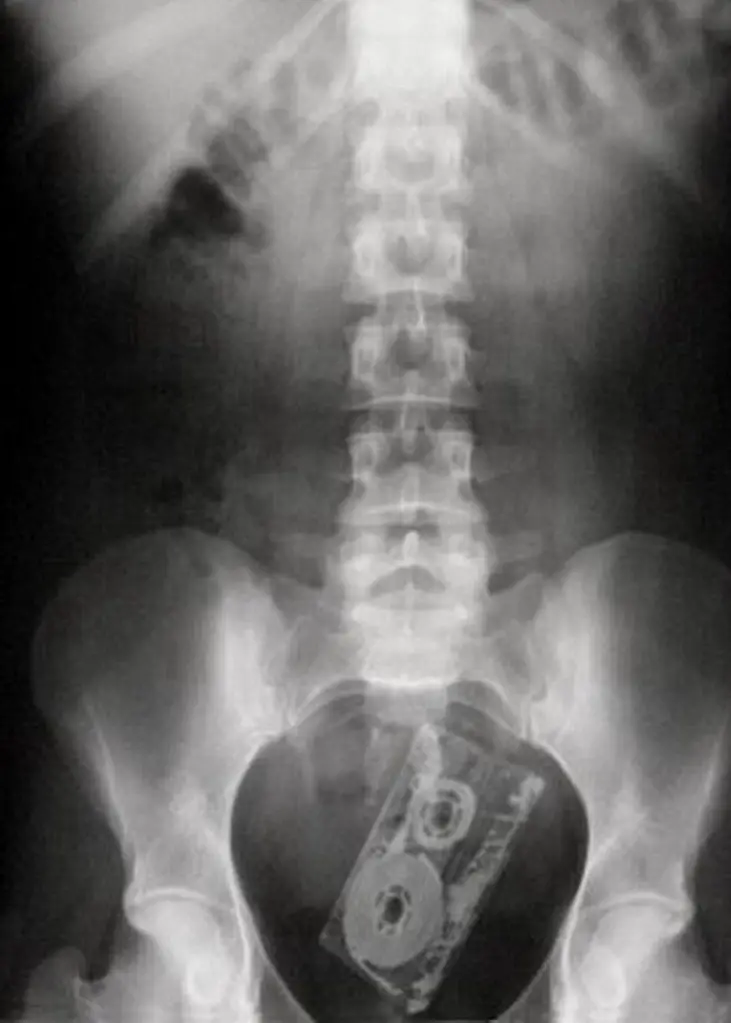

MEDICINA ONLINE OGGETTI CORPO ESTRENEO ANO BAMBINO ESOFAGO STOMACO BATTERIE SEX TOYS OGGETTI SESSO GIOCATTOLI TOSSICI BOTTIGLIA PENNA PENNARELLO COLON RETTO RISCHI COSA FARE COLONSCOPIA

Published 18/04/2018 at 1016 × 1423 in Corpi estranei nel tratto digerente: rischi e cosa fare in bambini e adulti

MEDICINA ONLINE OGGETTI CORPO ESTRENEO ANO BAMBINO ESOFAGO STOMACO BATTERIE SEX TOYS OGGETTI SESSO GIOCATTOLI TOSSICI BOTTIGLIA PENNA PENNARELLO COLON RETTO RISCHI COSA FARE COLONSCOPIA INTESTINO DIGERENTE RX RADIOGRAFIA